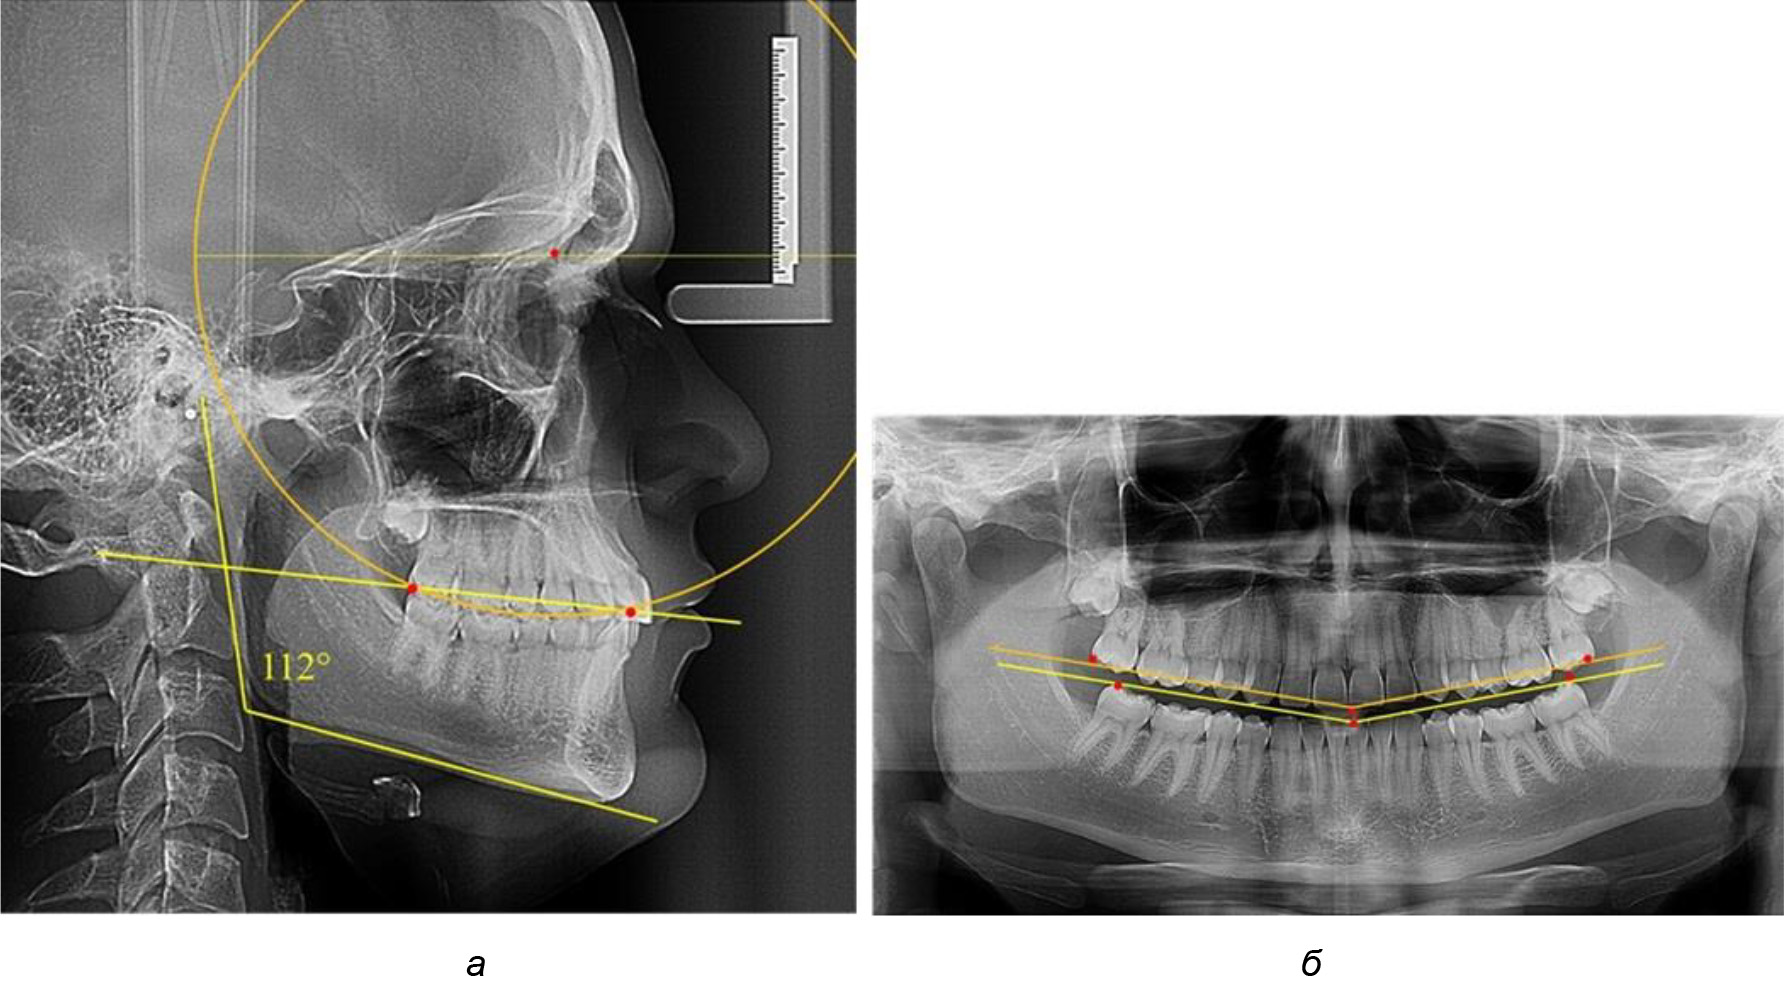

Деление величины радиуса круга к длине окклюзионной линии составило 1,623 ± 0,02. Таким образом, для определения радиуса окружности, соответствующей кривизне окклюзионного контура боковой ТРГ, необходимо измерить расстояние между передней и задней окклюзионными точками и последующим умножением полученной величины на число Фибоначчи (рис. 2).

Рис. 2. Особенности кривой Spee на ТРГ (а) и ОПТГ (б) у людей с признаками вертикального роста